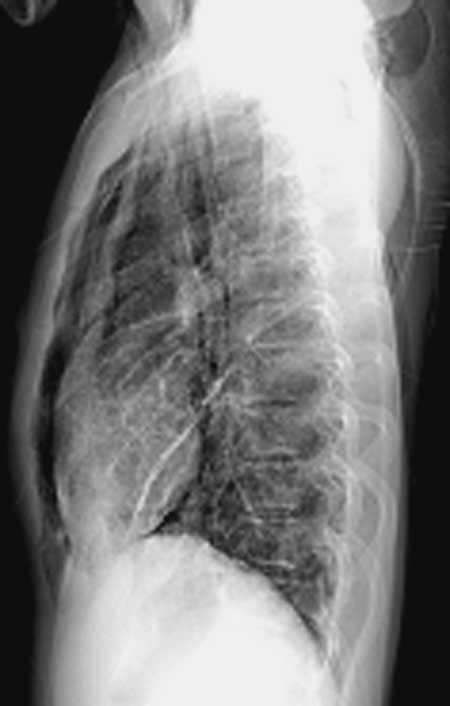

侧位胸廓前后径明显变小,心脏狭长.-------------扁平胸?--------需结合临床.

正位片摄片方式不对,肩胛骨未拉出,但从片上看就是两下肺透光度增强,考虑支扩可能性较大,侧位片不正,纵隔前缘考虑对侧胸廓影,因为两片放大率不知怎样,就从片子上看有直背综合征表现。

两肺纹理增多呈网络状,肺透亮度增强,于纵隔、胸骨后似见气体。不知病使,暂考虑间质性肺炎,纵隔气肿可疑。

王某某,男,16岁,既往无经常咳嗽、咳痰、胸闷、发热史,活动与同龄儿童相似,三月前突感胸、颈前痛、无喘憋,查体胸骨上皮下气肿,双肺呼吸音对称。胸部dr及ct示纵隔气肿,双肺囊肿。近两月反复出现胸痛、喘憋,无发热、黄痰及痰血,呼吸音减低,胸部dr示双侧自发性(张力性)气胸,胸腔闭式引流治愈。频繁发作,左侧引流两次,右侧引流三次。

1.诊断考虑先天性肺囊肿(囊性肺),自发性、张力性气胸,鉴别支气管扩张,先天性囊性腺瘤样畸形等

从上述x线片、ct片看,先考虑先天性肺囊肿(囊性肺),伴气胸、纵隔积气、皮下积气;先天性囊性腺瘤样畸形,一般中叶很少累及.